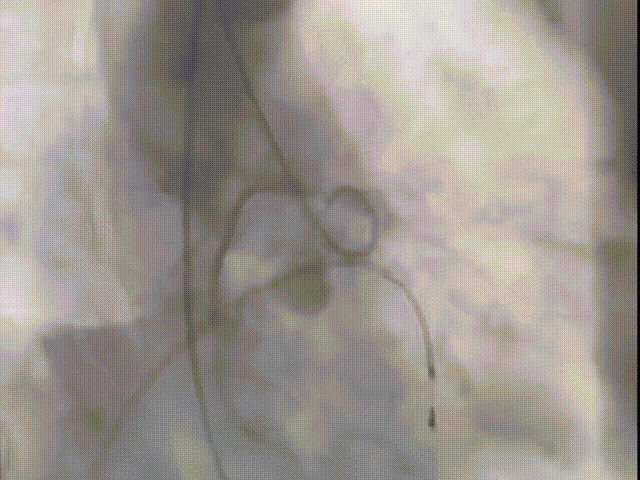

许金鹏教授 安徽省胸科医院 干瓣耐久首选之,15年承诺佑病患:随着病患的复杂性提高及TAVR二次手术窗口期的慢慢到来,摆在临床面前的是如何提升瓣膜使用的耐久性?预装干瓣的获批上市无疑为临床提供了全新的选择。预装干瓣摆脱了传统戊二醛保存的束缚,通过专利抗钙化技术及干式保存工艺打造了一款兼具“曲柔性”和“不沾钙”瓣叶的介入瓣,预期会有更耐久的使用寿命。此次病例患者小瓣环,Prostyle A®自膨瓣的收腰设计,为冠脉开口预留了“生命通道”,而平衡的收腰设计又很好的保证了开口面积,为小瓣环患者血流动力学提供的牢靠的保障。 期待这样一款基于临床需求的性能平衡的耐久干瓣,护佑 TAVR广大患者的全生命周期管理! 患者病史 主要诊断:非风湿性主动脉瓣狭窄(重度);非风湿性主动脉瓣关闭不全(中度);非风湿性二尖瓣关闭不全(中度);心脏扩大(左房明显扩大、左室略大);肺动脉高压(估测肺动脉收缩压约 39mmHg);胸椎压缩性骨折(T9 椎体,考虑新鲜);肺部阴影(两肺慢支改变、多发结节);胆囊术后; 入院检查:BP 109/60mmHg、心率 77 次 / 分(律齐),神清精神可,口唇不绀。 术前超声提示 主动脉瓣钙化并狭窄(重度)伴反流(中量),Vmax509cm/s,PGmax105mmHg;升主动脉增宽;左房明显增大,左室略大;二尖瓣关闭不全伴反流(中+量);瓣尖轻微增厚;室间隔增厚; 术前CT 三叶瓣(L-N融合,功能型二叶瓣),瓣叶增厚中度钙化,钙化主要分布在左冠窦瓣叶边缘及左无融合处、右冠瓣叶基底及边缘,主动脉瓣环径22.2mm,LVOT21.1mm,呈略直通型;双侧冠脉开口高度可,窦部空间大,VTC距离够,预估冠脉低风险,STJ、升主动脉内径可;左室内径可,主动脉水平夹角47°,非横位心。主动脉弓角弓距可;外周入路无明显迂曲,无钙化,两侧股动脉内径可,均可通过20F大鞘,右股低分叉。 手术策略 推荐右侧股动脉为主入路,左侧股动脉为辅助入路,使用20F大鞘,右股分叉上方1cm穿刺。推荐选择AV23瓣膜,18mm球囊预扩,最终理想位置瓣下2mm。 手术过程 在右股动脉穿刺建立通路后,顺利送入大鞘,经食道超声及血管造影确认路径稳定。18mm球囊预扩后评估冠脉灌注良好,后将Prostyle A® AV23瓣膜精准释放于目标位置,超声显示无瓣周漏,术后即刻造影显示无明显反流,导管测平均跨瓣压差8mmHg,心功能明显改善,患者生命体征平稳。 主动脉根部造影 18号球囊预扩 输送器顺利过弓 迅速锚定,平稳释放至工作位 最终造影,位置形态良好,无瓣周漏 Prostyle A®预装干瓣——助力临床最优化解决方案 预装干瓣 便捷顺安:金仕生物专利抗钙化技术运用纳米技术去除组织内的细胞碎片和磷脂,封闭游离醛基,从根本上阻断了瓣膜钙化的多项因素,显著提升了瓣膜的耐久性;同时,相比较传统戊二醛保存方式,干式存储最大限度的保留心包的亲水亲油平衡,还原组织天然曲柔性,进一步保障了瓣叶开合,保证长期耐久性; 流入端桶状设计:流入端桶状的设计,迅速稳定锚定,减少手术时间的同时进一步保障了术中安全; 平衡的收腰设计:该病例左冠高度10.8mm,AV23瓣膜的平衡收腰设计既确保了冠脉开口安全性,又保证了EOA,有效降低了循环崩溃风险,而术后8mmHg的压差的表现更加证明了优秀的血流动力学,进一步提高了瓣膜的耐久性。 专家简介 许金鹏 安徽省胸科医院(点击查看专家详细简历) · END ·